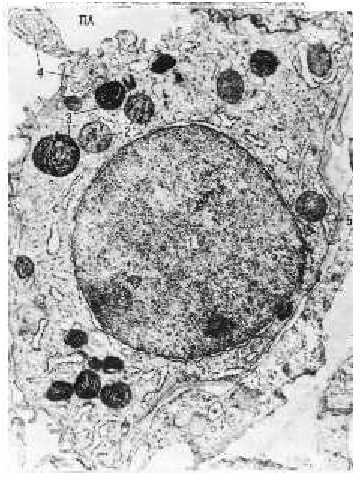

| Электронная микрофотография. Альвеолоцит 2-го типа в стенке альвеолы. | ||

| Морфо- логия альвеоло- цитов-II | 1.а) Кроме обычных органелл – ядрá (1), митохондрий (2), развитой ЭПС и аппарата Гольджи, – альвеолоцит 2-го типа содержит в цитоплазме слоистые,или пластинчатые, тельца – цитофосфолипосомы (3). б) Основной компонент последних – фосфолипиды; по этой причине тельца являются осмиофильными. 2. а) Некоторые фосфолипосомы (4) находятся в процессе выделения в просвет альвеолы. | |

| б) Далее из их материала и будет формироваться мембранная фаза сурфактанта. 3. Базальной своей стороной альвеолоцит 2-го типа лежит на базальной мембране (5) альвеолярного эпителия. | ||